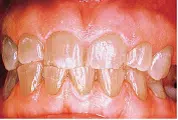

Dentinogenesis Imperfecta

این ناهنجاری اتوزومال غالب است و تکامل غیر طبیعی عاج شیری و دائمی را بدنبال دارد. دارای سه نوع 1 و 2 و 3 می باشد. هر سه نوع DI  توبول های عاجی نا به جا و در جهات نا مناسب تولید می کنند . دندان های شیری شدید تر از دندان های دائمی مبتلا می شوند به نحوی که آخرین دندانی که رویش می یابد از همه دندان ها درگیری خفیف تری بروز می دهد. دندان های یاد شده از لحاظ کلینیکی هنگام رویش ظاهر طبیعی دارند ولی در طول مدت کوتاهی تغییر رنگ یافته و به رنگ کهربایی تا خاکستری –قهوه ای یا شفاف دیده می شوند. مینا از روی این عاج ناقص به صورت لایه لایه کنده شده و باعث ایجاد شیارها و سایش قابل توجهی می شود.